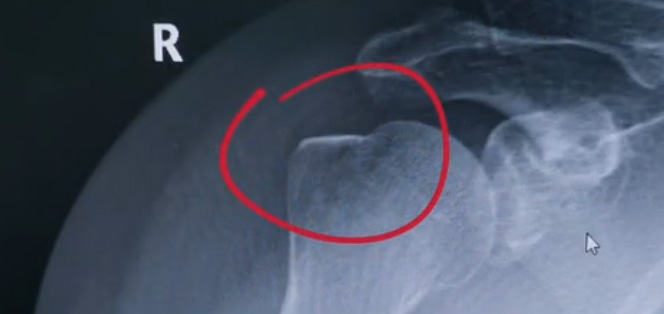

肩關節的X射線片子,看到沒有明顯的骨折,但是實際上已經骨折了。那么是如何發現的呢?醫生對于做出疾病診斷的時候,會選擇什么樣的檢查方式。也更好的配合醫生,來解決問題。1米高的地方摔了下來,右側肩關節與地面相撞受傷了。當時的胳膊還能活動,疼痛感很明顯,但是在家觀察了一天,這個腫脹沒有明顯的加重。然而問題是什么呢?疼痛始終不能緩解,所以就需要到醫院檢查。醫生查看關節的受限也很明顯,尤其做外展這個動作的時候,幾乎沒辦法自行完成。肩關節內的這個韌帶和肌腱可能還沒有發生嚴重的損傷。

首先做一個普通的X光檢查,看一看有沒有大的骨折或大的問題。結果是沒有發現太嚴重骨折損傷問題。結合病史,還是有點疑惑。因為疼的太厲害。x光檢查和他的疼痛之間不匹配,患者沒有骨頭的損傷,疼痛不至于達到這么嚴重的一個程度。是否有一種情況掩蓋住了病情。這也是X線檢查的通病。x光檢查它是一個二維的檢查,有可能患者肩關節啊發生了骨折。但是它的位置被前方或者側方的這個骨頭遮擋住了。不是立體的就沒辦法看到后方的情況。想要更加進一步的明確問題,判斷是否有骨頭的損害怎么辦?

進一步就是查CT,可以更全面的角度去判斷問題的所在。就會發現是否骨折可以看到確實存在著骨折,還好骨折不算嚴重??梢哉f是一個骨裂。這個肩關節與地面撞擊的時候,暴力沒有達到那么強。讓骨頭整個發生一個巨大的斷裂,而是造成了一個小的劈裂。適當的進行一些抗炎止痛藥的使用。適當的進行一些消腫治療,患者癥狀也就消失了。